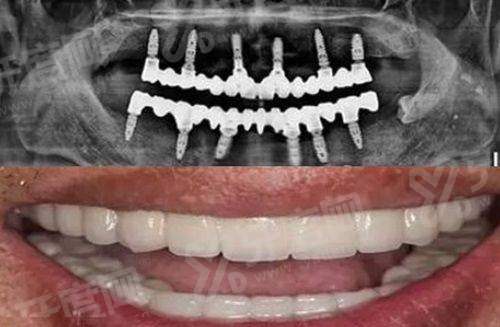

1. 特别多人关心乌鲁木齐双宝口腔靠谱吗,其实看技术便知,医院引进数字化导板种植技术,能精细定位种植体位置。

2. 通过 CBCT 三维成像重建口腔数据,术前模拟手术路径,避开神经血管,大幅降低手术风险与创伤。

3. 支持即刻种植修复,缩短缺牙等待期,让中老年患者也能快速修复咀嚼功能,技术成熟度较高。